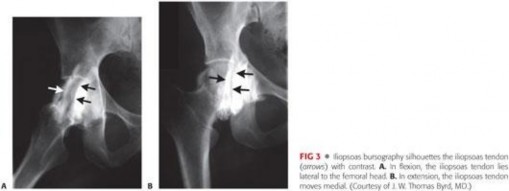

The mechanics of the snap itself are a product of the tendon's path over the anterior hemipelvis. In flexion, abduction, and external rotation (the FABER position), the tendon lies lateral to the center of the femoral head. As the hip is brought into extension, adduction, and internal rotation, the tendon abruptly translates medially across the iliopectineal eminence and the anterior femoral head. If the tendon is abnormally tight or the bursa is inflamed and thickened, this translation is no longer smooth, resulting in the characteristic mechanical "clunk."

Standard radiographic evaluation includes an AP pelvis, false profile, and Dunn lateral views to assess for dysplasia, FAI (cam/pincer morphology), and joint space narrowing. Magnetic Resonance Arthrography (MRA) is the gold standard for evaluating the labrum, articular cartilage, and the iliopsoas tendon. MRA can reveal tendinosis, peritendinous edema, bursitis, and the characteristic 3 o'clock anterior labral tear associated with psoas impingement. Dynamic ultrasound is highly valuable for visualizing the tendon snapping in real-time over the iliopectineal eminence.